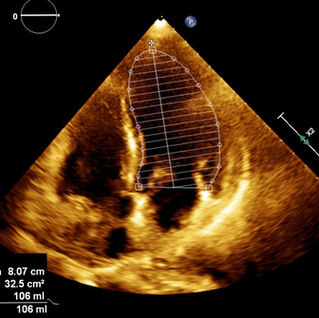

2. Biplane disk summation (beyond FoCUS)

Lets now move beyond the scope of a Focused cardiac exam and look at the current recommendations for estimation of LV EF. Volume measurements are usually based on tracings of the blood-tissue interface between compacted myocardium in the apical four- and two-chamber views and. At the mitral valve level, the contour is closed by connecting the two opposite sections of the mitral ring with a straight line. LV length is defined as the distance between the middle of this line and the most distant point of the LV contour. This method corrects for shape distortions and uses less geometrical assumptions compared to linear models (seen next). Ultrasound machines may have this feature built in.

LV EF calculation by Simpson's method. 1 is a still image at end diastole on the apical 4 chamber view. 2 is a still image on the same view but at end systole. 3 is a still image at end systole and its companion at end diastole is not displayed. LV EF is thus calculated LVEF= (LVED-LVES)/LVED.